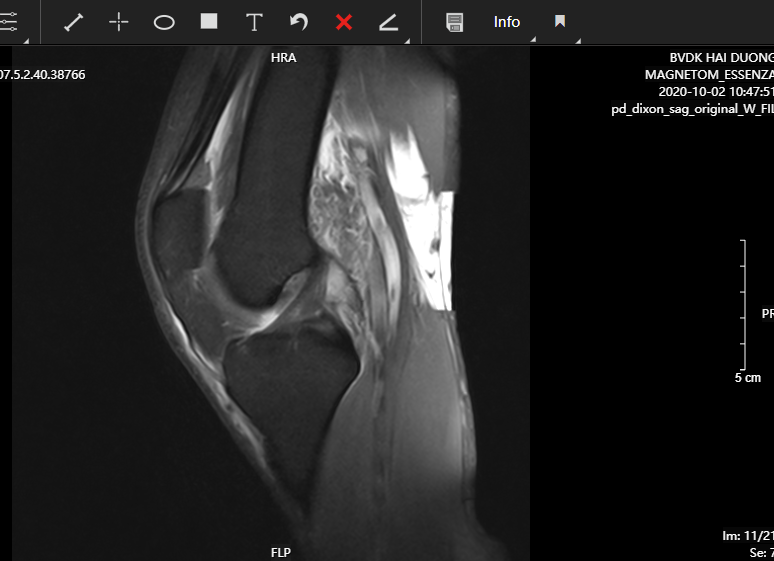

Giá trị của cộng hưởng từ khớp gối chẩn đoán tổn thương dây chằng chéo trước trong chấn thương

Chấn thương khớp gối gặp ngày càng nhiều trong thực tế lâm sàng, chẩn đóa chính xác tổn thương sẽ giúp điều trị phục hồi chức năng vận động khớp gối kịp thời và hiệu quả